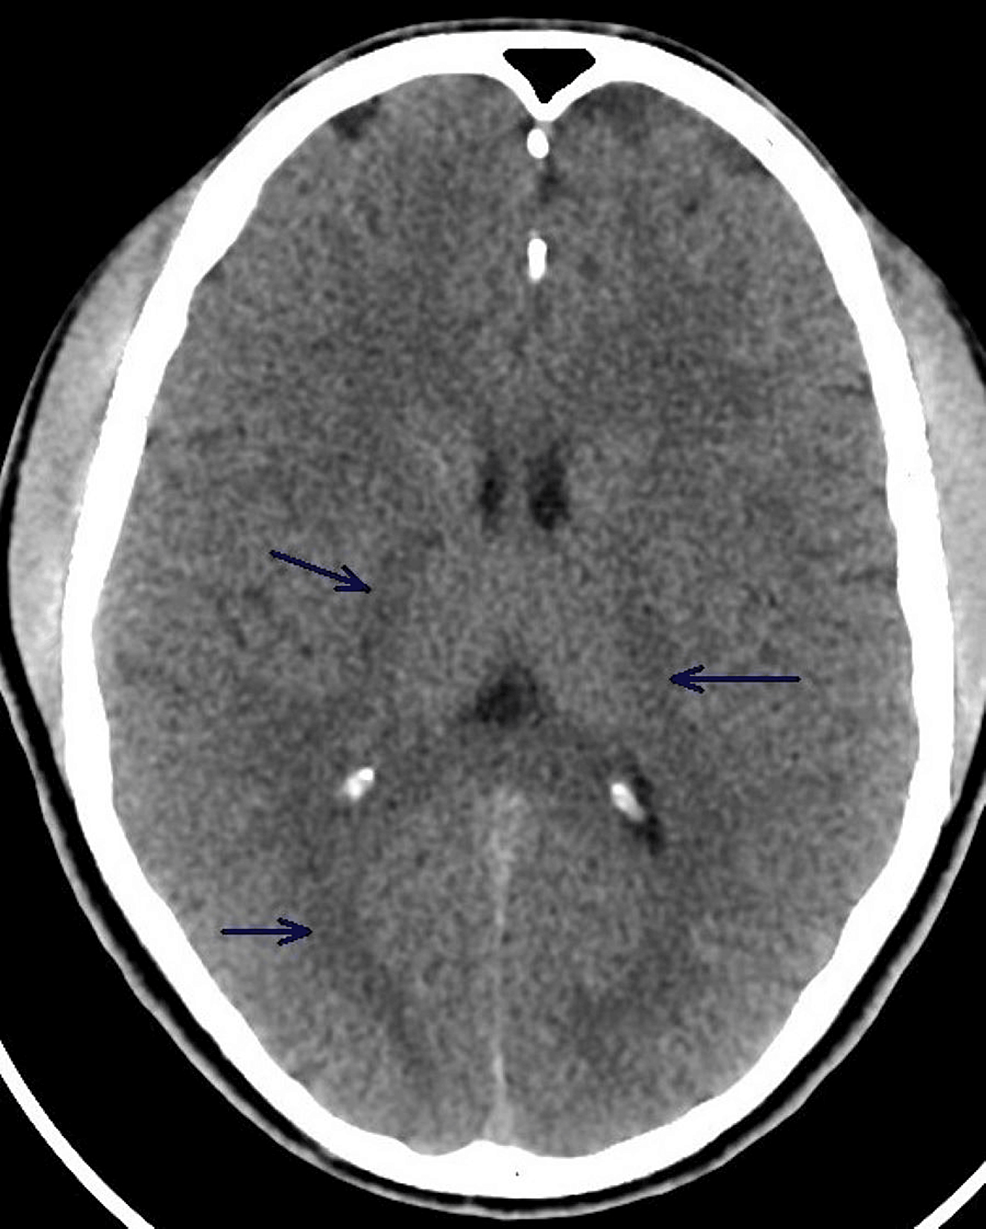

Case 252: Acute Hyperammonemic Encephalopathy Resulting from Late-Onset Ornithine Transcarbamylase DeficiencyRadiology

Case 252: Acute Hyperammonemic Encephalopathy Resulting from Late-Onset Ornithine Transcarbamylase Deficiency | Radiology